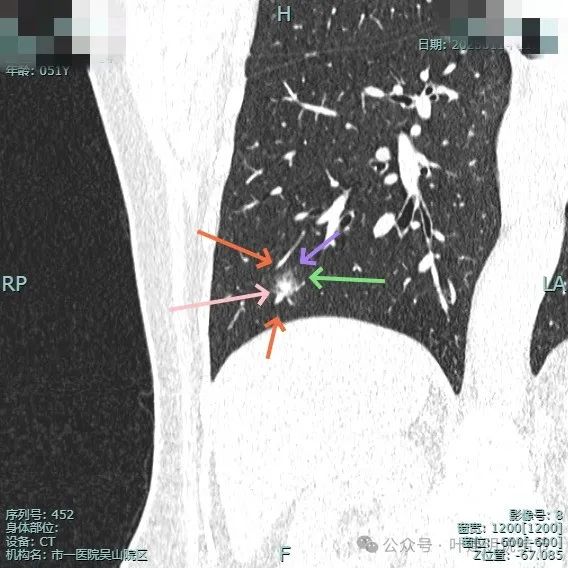

右下病灶混合密度,整体轮廓较清,但瘤肺边界欠清晰。

实性成分占比高,边缘看上去有晕似的,边上有明显血管走行。也有细支气管可见。

实性部分或整体病灶缺乏收缩力,膨胀感也不明显。瘤肺边界欠清晰,感觉有一圈晕。

晕征上图更明显,进入的血管未见明显异常增粗,略显弯曲。